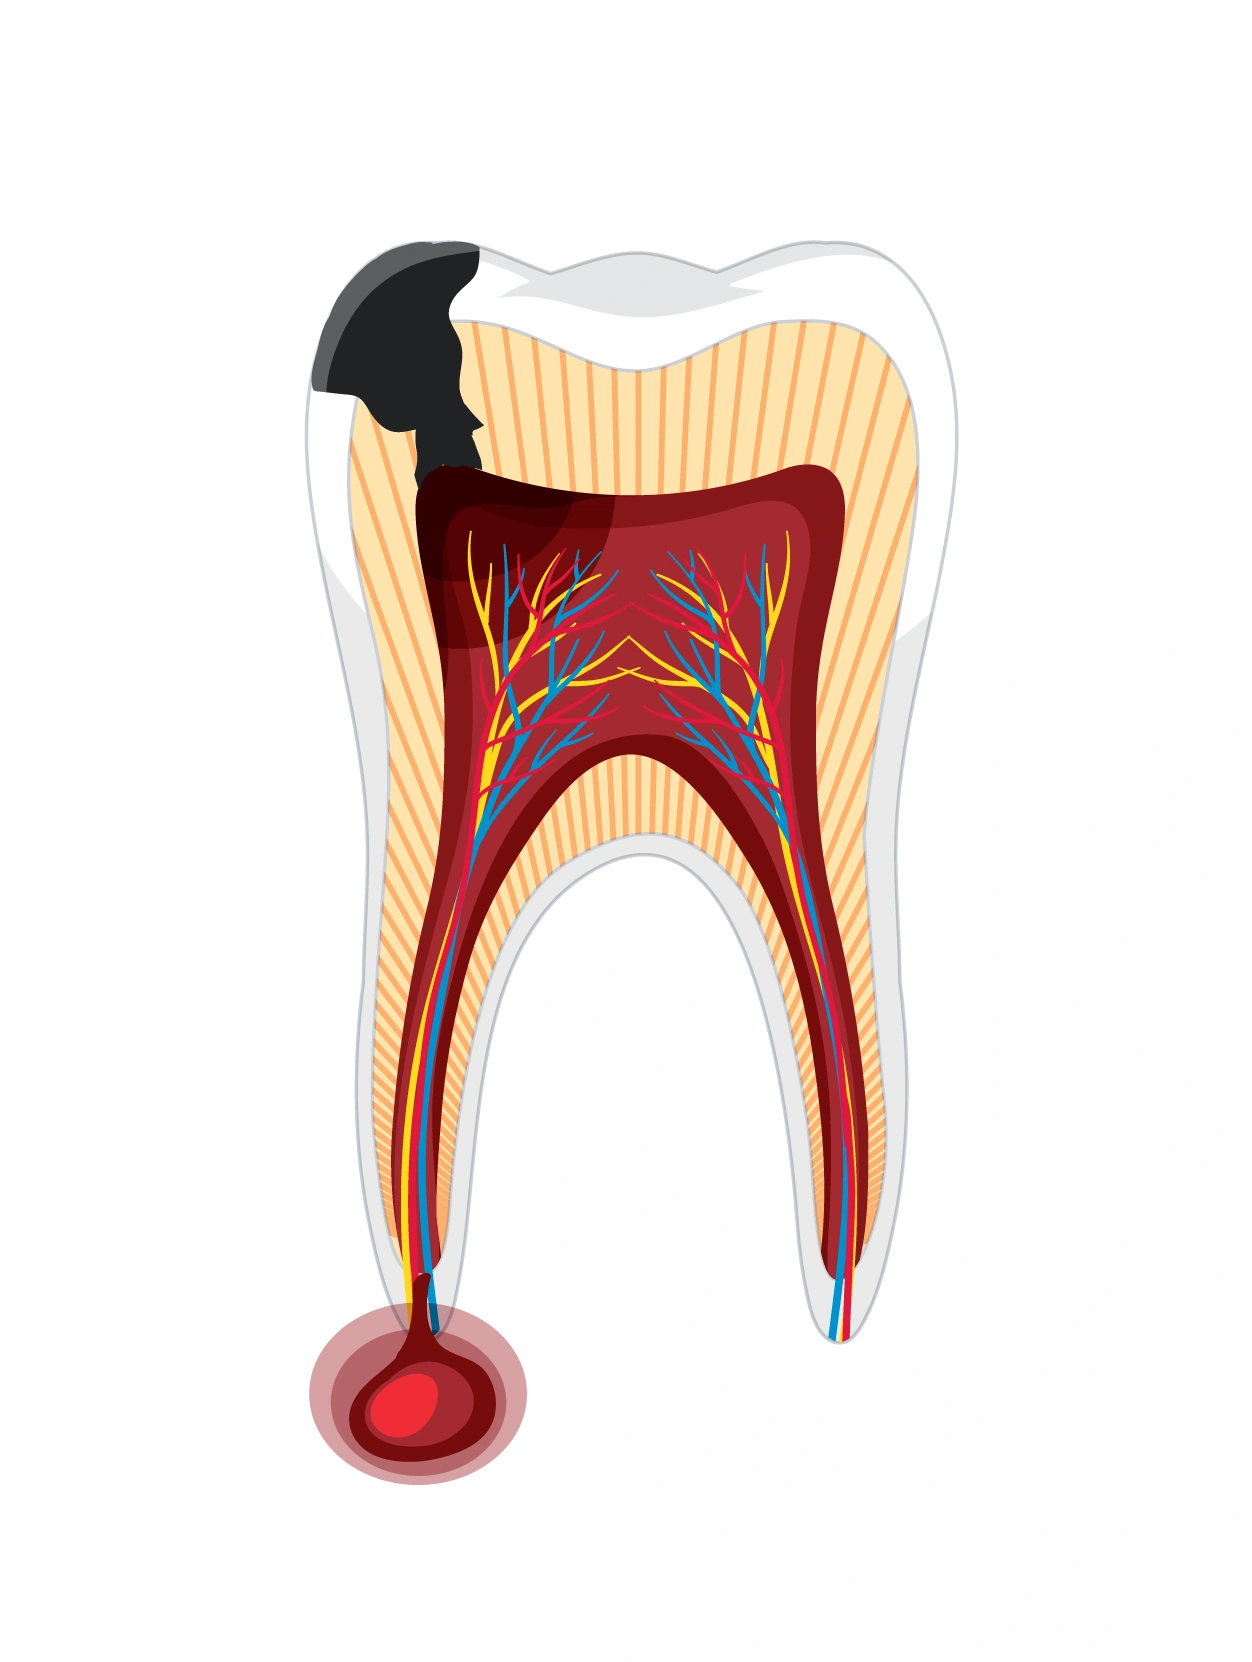

A root canal is needed when decay, injury, or infection reaches the tooth’s inner pulp, causing pain, sensitivity, or swelling. The infected tissue is removed, the canals are thoroughly cleaned, disinfected, and sealed, and the tooth is later strengthened with a crown to restore full function.

A root canal works by eliminating infection from inside the tooth and protecting it from recurring damage.